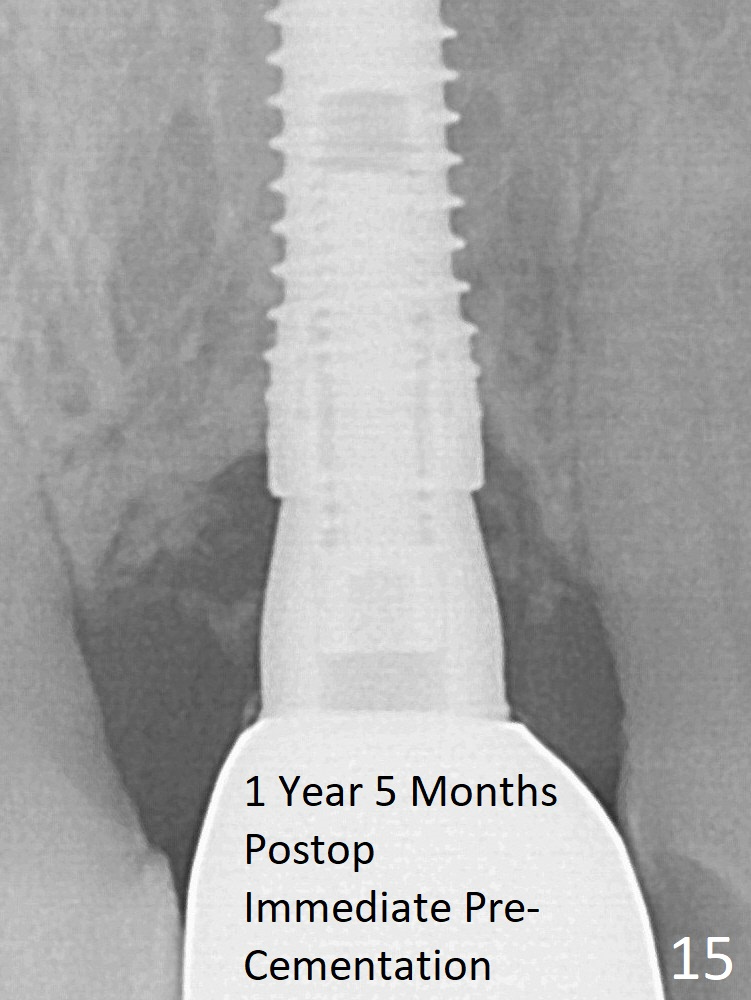

The mesial defect is filled with Vera Graft (Fig.7 *) and heals 1 year 4 months postop (Fig.11). The implant could be placed ~ 1 mm deeper (Fig.15).